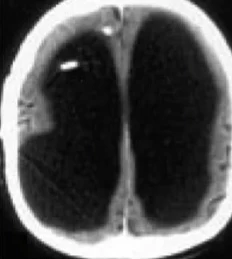

در نمونه ای نادر، یک فرد با از دست دادن حدود ۹۰ درصد از مغز خود همچنان از هوشیاری کامل برخودار است. این اتفاق باعث شده که دانشمندان بار دیگر بر نظریههای خود و تعریف هوشیاری از نظر بیولوژیکی بازنگری کنند. با زومیت همراه باشید تا در مورد این نمونهی پزشکی بیشتر بحث کنیم.